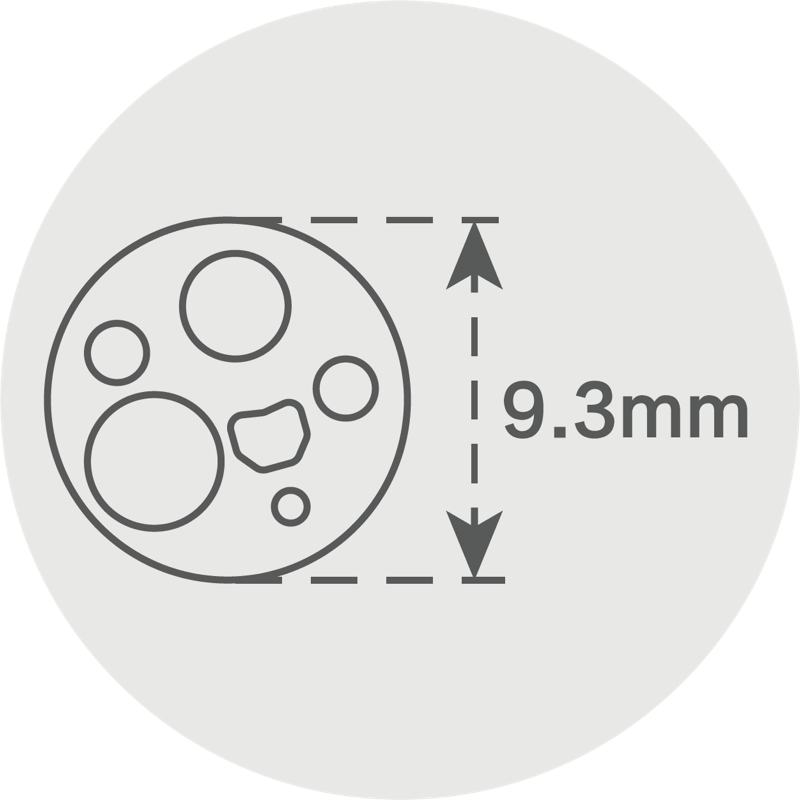

胃镜具有9.3mm的纤细外径。

头端部外径: 9.3mm

插入部主软管外径: 9.3mm